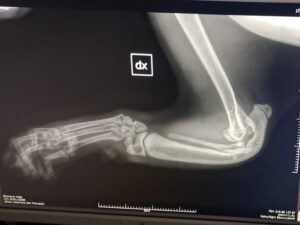

Denn inzwischen wurde Pino auf Sardinien untersucht und geröntgt. Es war sehr stark zu erwarten, dass es sich um eine angeborene Anomalie handelt. Und dies ist auch so. Pinos „Ellenknochen“ (Radius) fehlen auf der einen Seite ganz, auf der anderen Seite ist er unterentwickelt. Das führt dazu das seine Füßchen mit den Ellenbogen nicht stabil verwachsen sind und die Gelenke nicht festsitzen. Dadurch wachsen auch die Knochen nicht entsprechend und haben krankhafte Veränderungen.

Der kleine Mann ist eine „Känguru-Katze“, seine verkürzten Vorderbeine wird er nie richtig belasten können, so wie es im Moment aussieht. Ein normales Katzenleben in Freiheit ist für ihn unmöglich. Gott sei Dank zeigen sich aber keine andere Anomalien in seiner Anatomie.